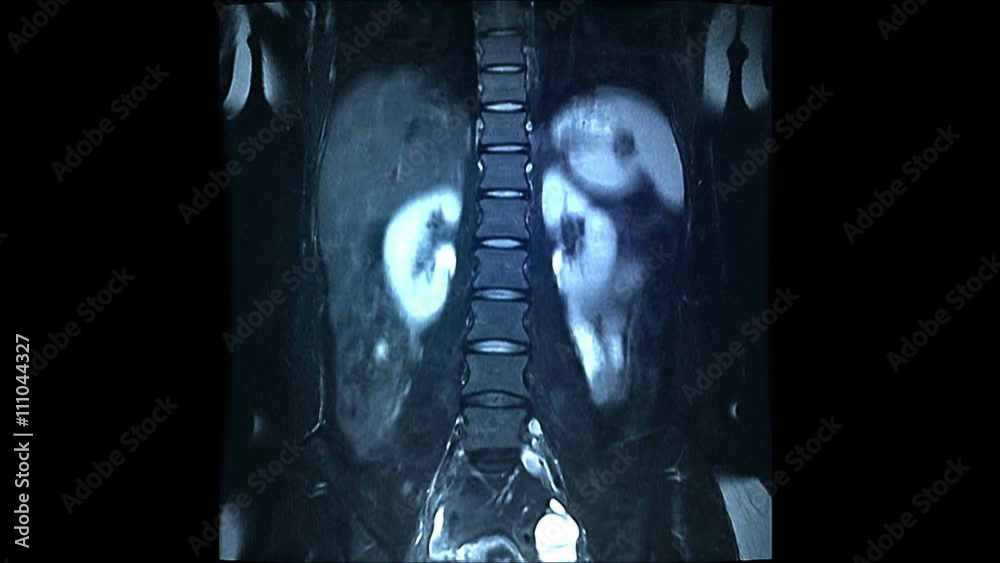

Em imaging

Em imaging 57 фотографий